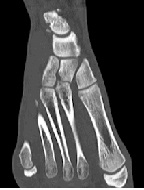

Isolated Dislocation of the Medial Cuneiform Bone: A Case Report

Lonnie Froberg*, Jesper Kampp Holm, Hagen Schmal